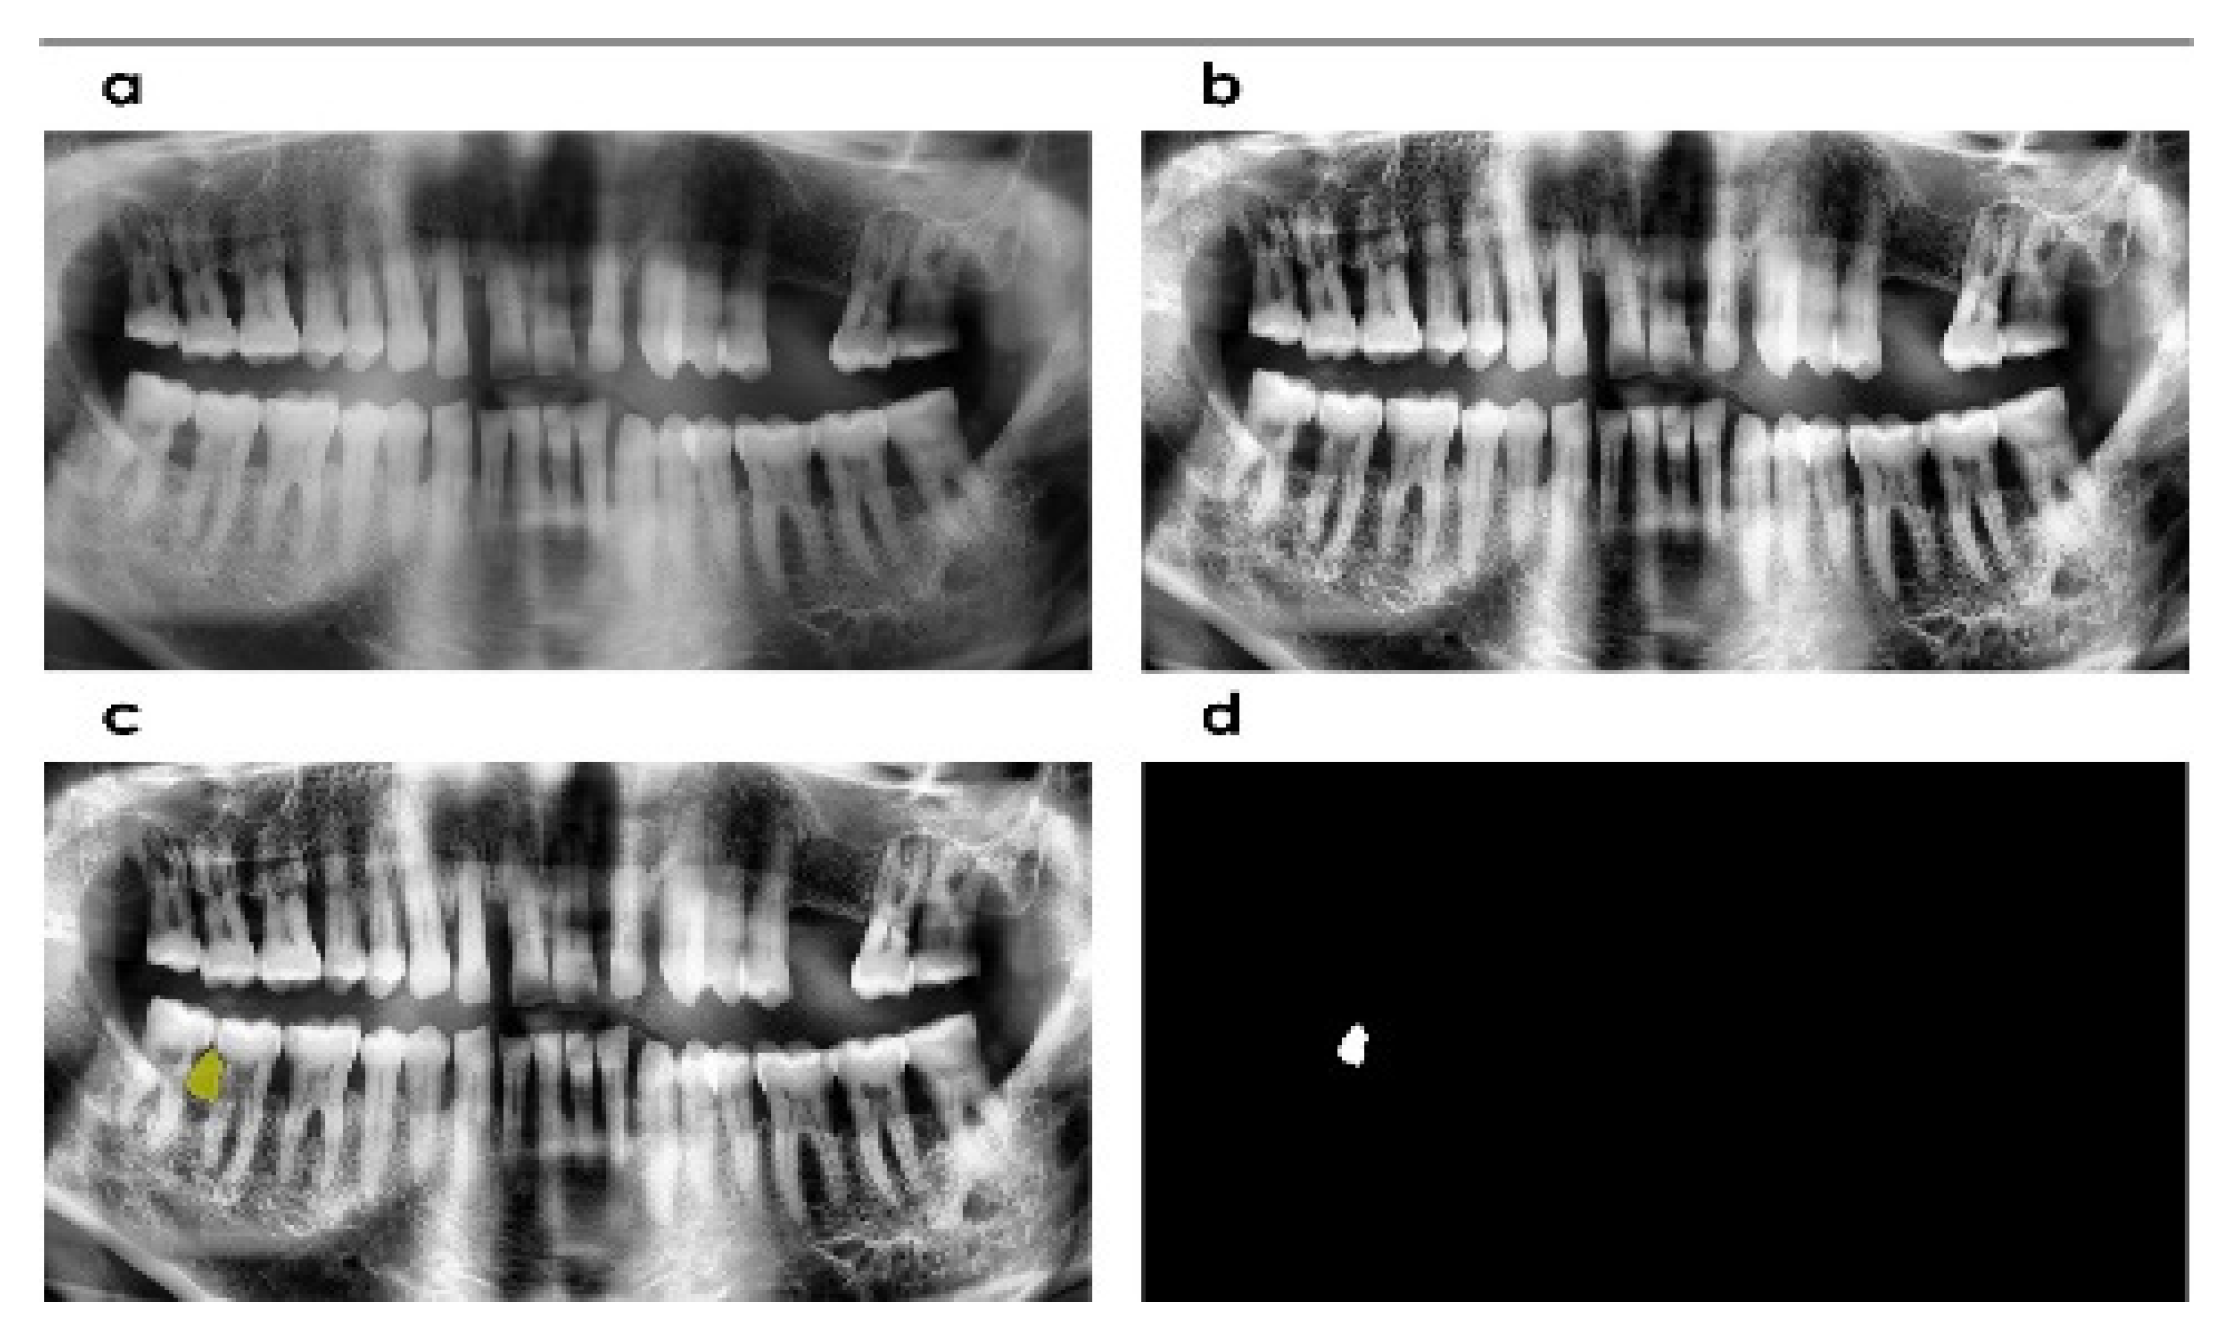

2.2. Computational Tool

2.3. Image Enhancement

2.5. Segmentation